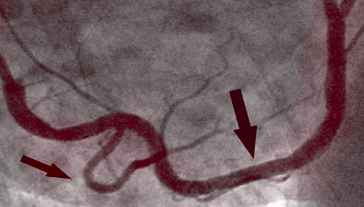

PO

Na sliki desno vidimo, kako je videti očiščena koronarna arterija, že brez sledi poapnele aterosklerotične lehe. Ni oblog holesterola. Kri teče prosto in oskrbuje s kisikom vse organe.